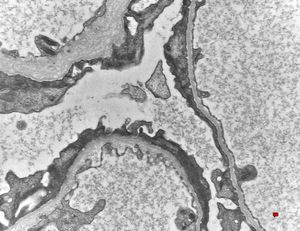

M,6y. | Alport syndrome- digital photo from the screen